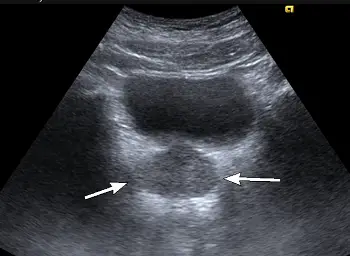

附圖為骨盆腔超音波橫向掃描,箭號所指為何?

本題測驗骨盆腔超音波(Pelvic Ultrasound)的解剖構造辨識,特別是男性骨盆腔在經腹部超音波(Transabdominal Ultrasound)橫切面(Transverse scan)下的解剖相對位置。在進行男性骨盆腔掃描時,通常會利用漲滿的膀胱作為音窗(Acoustic window),以利於觀察其後下方的攝護腺及周邊構造。

- 探頭位置與掃描切面:這是一張經腹部超音波的橫切面(Transverse view)影像。

- 無回音(Anechoic)區域:影像中上方呈現大範圍黑色、無回音的囊狀構造,這是充滿尿液的膀胱(Urinary bladder),在此扮演極佳的音窗角色,使得後方的組織得以清晰成像。

- 箭頭所指之構造:白色箭號指著位於膀胱正後下方的一個實質(Solid)、呈現中度回音(Mid-level echogenicity)、外觀略呈橢圓形且邊界尚稱清楚的腺體構造。根據男性骨盆腔的解剖位置,此緊鄰膀胱頸下方的構造即為攝護腺(Prostate)。

- (A) 膀胱(Urinary bladder):在影像中為上方大面積黑色無回音(Anechoic)的液體區域。箭號並非指向此處。